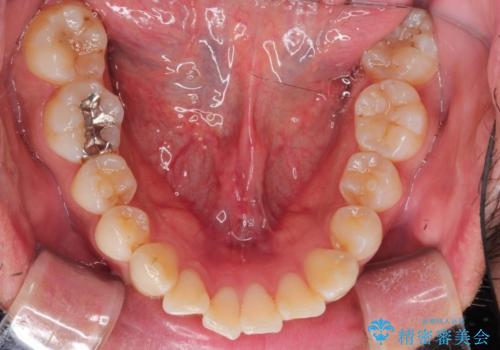

【インビザライン】前歯の凸凹を解消。

- 前歯の凸凹を主訴に来院されました。

もともと、顎が左にシフトしていたので正中が合わないことを説明した後、矯正を開始しています。

短期間で前歯のがたがたがきれいになり、満足していただけました。